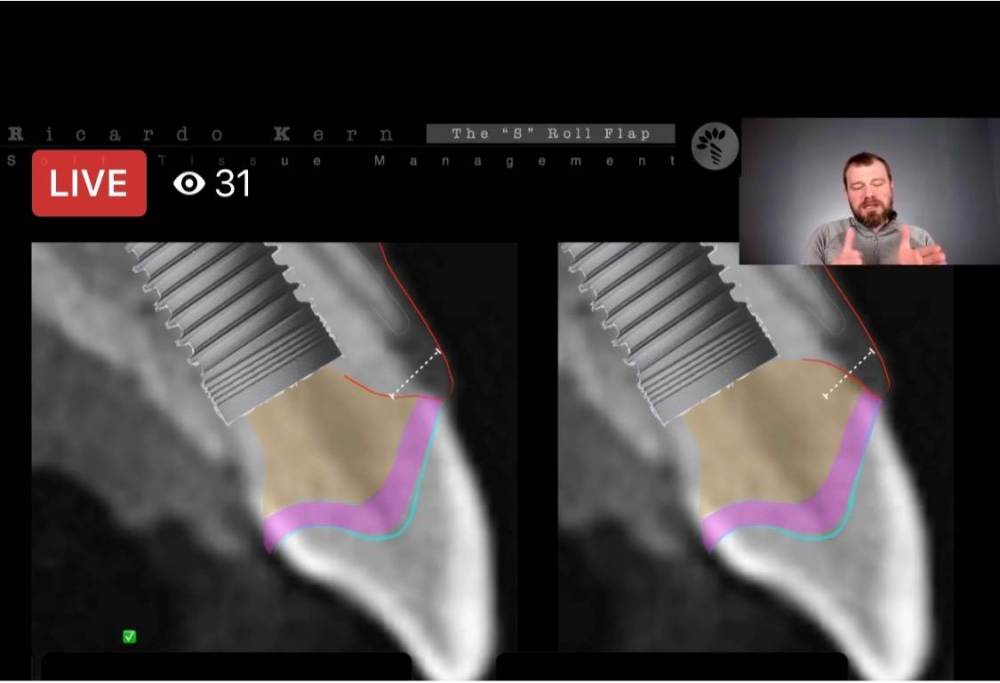

колесников Опубликовано 1 июля, 2022 Поделиться Опубликовано 1 июля, 2022 Все ошибки верно отметили. Выбор пациента,тактика лечения,предварительная работа с мягкими тканями,временная конструкция. И вот тут некому было подсказать-вид временной конструкции. Во фронте и для этого уже есть протоколы,хорошо о них рассказывает Рикардо Керн,Руслан Хатит,у Рауф Алиева на имплантариуме найдёте также запись по теме,да все кто показывает работы и читает лекции во фронте обязаны говорить о деталях протокола. Работа с мягкими тканями одновременно с имплантацией (тут была ошибка -ее не было) положение платформы импланта относительно зенита 3-5мм направление выхода шахты небно временная конструкция(супраструктура ключевой момент в формировании каркаса прикреплённой слизистой , ошибка 2-не было нагрузки. Ошибка3-съемная конструкция) вид временной конструкции(вестибулярно балкон,максимально заужено в основании ,апроксимальные пространства не задавливают сосочки) Ошибка4-смена врача и необозначены эстетические риски и этапность протокола,сроки. по вашей работе:сст брали не там ,клали не туда,шили не так. если хотите получить сосочек на этом этапе,надо дорабатывать реставрации и делать вертикальную десневую аугментацию по Сузуки -Масана и ждать ещё 2-3 месяца. 1 1 2 Ссылка на комментарий